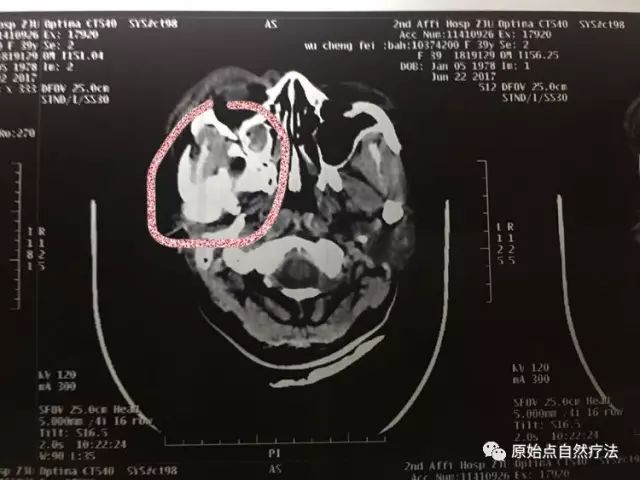

- 上下頜骨CT檢查顯示:右上颌窦前外壁及右眼眶外侧壁多发骨折碎骨片形成。

- 右侧颌面软组织肿胀、积气伴血肿形成。左侧颌面部软组织稍肿胀。

- 影像所示:右上颌窦前外壁及右眼眶外侧多发骨折,碎骨片形成,右侧颌面部软组织肿胀、积气伴血肿形成:左側颌面部軟組織稍腫脹。

上下頜骨CT檢查顯示:右上颌窦前外壁及右眼眶外侧壁多发骨折碎骨片形成。右侧颌面软组织肿胀、积气伴血肿形成。左侧颌面部软组织稍肿胀。

影像所示:右上颌窦前外壁及右眼眶外侧多发骨折,碎骨片形成,右侧颌面部软组织肿胀、积气伴血肿形成:左側颌面部軟組織稍腫脹。

右眼眶骨折

右颌骨骨折

右眼眶外側壁多發骨折,碎骨片形成。

积氣伴血腫形成